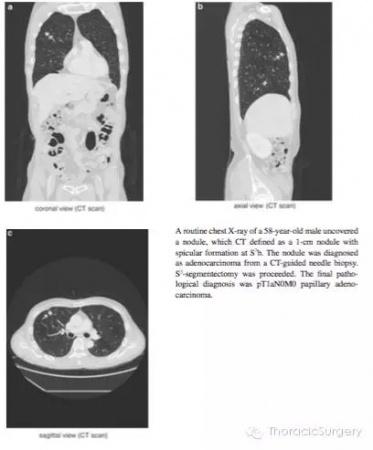

患者,男性,58岁,常规胸片发现右上肺结节。CT可见一S3b的1cm结节,周围伴有毛刺。CT定位下活检病理证实为肺腺癌。予以S3肺段切除。最终的病理学诊断为pT1aN0M0**状腺癌。

图.3.3.1 通过HRCT影像从轴状面,冠状面和矢状面明确肺段动脉,静脉和支气管。气管插管后通过支气管镜进一步明确B1,B2和B3分支形状和尺寸。本书中的图片是段支气管和动脉最常见的分支类型,即右上支气管分为B1和B2和B3;A1和A3段间动脉分支源于肺动脉上干。A2a是源于肺动脉上干的反支,A2b为A2的升支;段间静脉源于尖段和中央静脉。第三肋间推荐作为S2段切除的主操作孔。